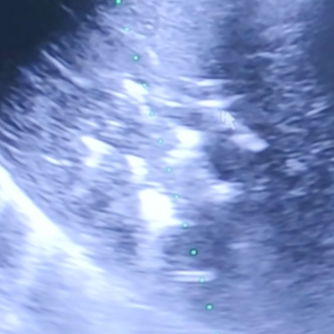

“这个甲状腺瘤比较大,血供也比较丰富,临近周边组织血管,手术有一定风险。但我们可以在超声可视化引导下,避开颈部丰富的神经及血管,将一根‘针’插到肿瘤内,用‘热’把肿瘤杀死。”这个“热”消融,也就是微波消融术,我们利用“移动消融“的方法,把大的肿瘤分成不同部分分别消融,像工匠雕刻一样,才能把边边角角都消融干净。

甲状腺瘤微波消融。像工匠雕刻一样,“移动消融“的方法,把大肿瘤分成不同部分分别消融。

2008年Jeong等在甲状腺射频消融治疗中首先提出了“moving-shot technique”,即移动消融的方式,通过针尖移动形成多个大小不等的消融单位从而覆盖整个病灶,在后续临床实践中取得了良好的疗效。Lim等随访(49.4±13.6)个月,结节平均缩小率达到(93.4±11.7)%。相比之下,移动消融灵活性较高,消融单位大小可通过改变针尖移动的速率来调整。

对于周边邻近危险结构的位置,可通过加快移动速度、采用相对较小的消融单位来覆盖;对于血流丰富的位置,还可以通过提高功率和减慢移动速度,甚至过渡至固定消融使该位置组织坏死更彻底,确保消融的安全性和长期疗效。